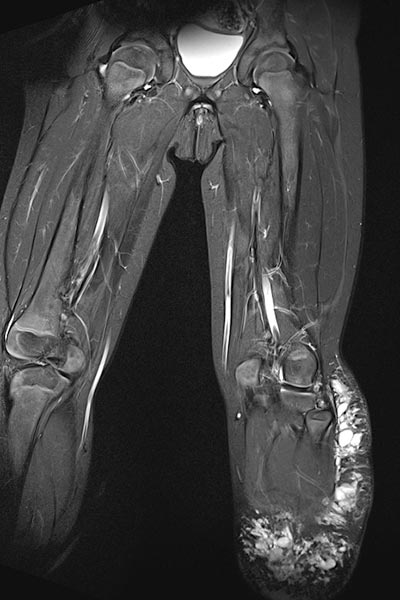

Die koronare Magnetresonanztomographie in T2-Wichtung, fettgesättigt, zeigt die stark hyperintense (fast weiße), zum Teil zystische Läsion am linken Bein im subkutanen Fettgewebe.

In der Magnetresonanztomographie in T1-Wichtung, fettgesättigt, nach Kontrastmittelgabe zeigt die Läsion am linken Bein im subkutanen Fettgewebe keine zentrale Kontrastmittelanreicherung. Allenfalls die Zystenwände reichern zart Kontrastmittel an (Ausschnittvergrößerung rechts). Somit im MRT das Bild einer lymphatischen Malformation.